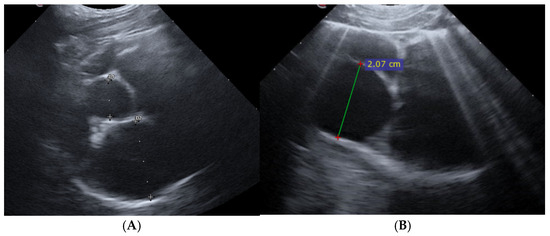

Background and Clinical Significance: Mechanical complications and intracavitary thrombus are both recognized causes of clinical deterioration following acute myocardial infarction, yet they require fundamentally different therapeutic approaches. Distinguishing between these entities is critical, as misdiagnosis may lead to unnecessary surgical intervention or delayed [...] Read more.

Background and Clinical Significance: Mechanical complications and intracavitary thrombus are both recognized causes of clinical deterioration following acute myocardial infarction, yet they require fundamentally different therapeutic approaches. Distinguishing between these entities is critical, as misdiagnosis may lead to unnecessary surgical intervention or delayed anticoagulation with serious consequences. Left ventricular (LV) thrombus typically appears as a well-defined mass; however, atypical and highly mobile morphologies may closely mimic catastrophic post-infarction mechanical complications, creating significant diagnostic uncertainty. This case highlights the pivotal role of contrast-enhanced echocardiography in resolving such ambiguity and guiding appropriate management in a high-stakes clinical setting. Case Presentation: A 60-year-old man presented with acute dyspnea and pulmonary edema ten days after an anterior myocardial infarction treated with percutaneous coronary intervention, complicated by ischemic stroke. Transthoracic echocardiography demonstrated severe LV systolic dysfunction with moderate-to-severe mitral regurgitation and an unexpected, highly mobile, irregular mass protruding into the LV apex. The mass exhibited a shredded, tissue-like appearance, raising urgent concern for post-infarction mechanical complications, including papillary muscle rupture or apical myocardial disruption, and prompting immediate consideration of surgical intervention. Contrast-enhanced echocardiography was performed and revealed a mobile LV apical thrombus. Surgical management was avoided, and systemic anticoagulation was initiated, followed by transition to rivaroxaban in combination with ongoing dual antiplatelet therapy. The patient demonstrated rapid clinical improvement with optimized heart failure treatment and was discharged after four days, with planned follow-up imaging to assess thrombus resolution. Conclusions: Left ventricular thrombus may present with atypical, misleading morphologies that closely resemble life-threatening mechanical complications after myocardial infarction. Full article